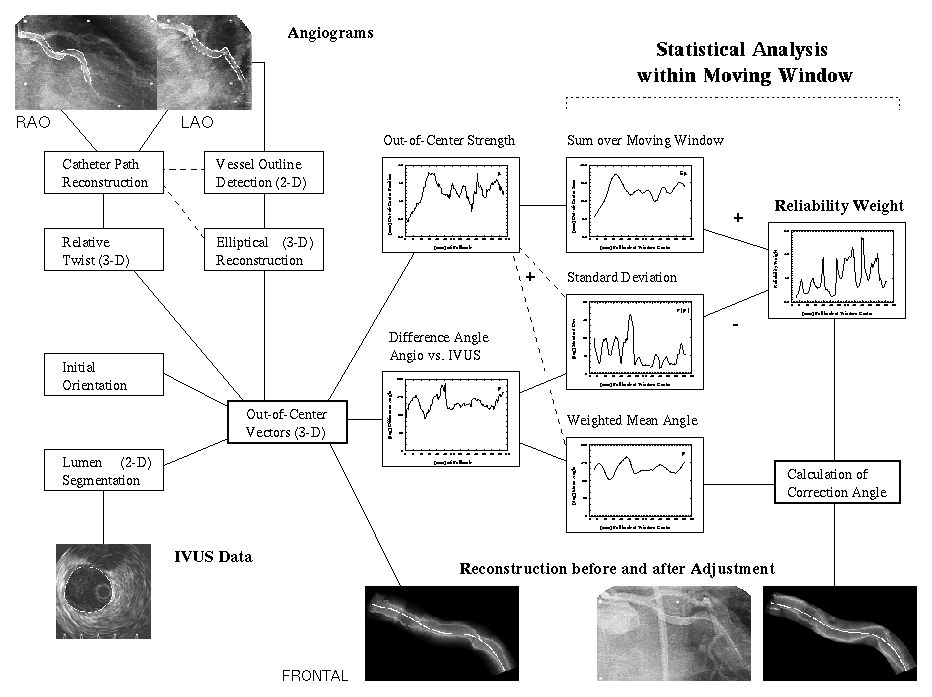

Flow Diagram of Absolute Orientation System